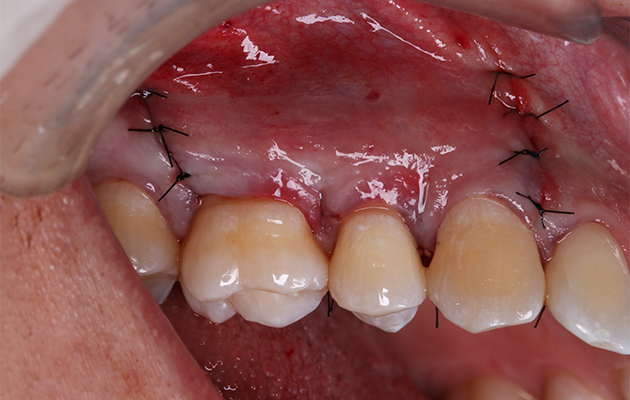

17 | Síntese.

Enquanto parte da coleta sanguínea é destinada à incorporação junto ao biomaterial, outra parte é segregada para a polimerização da fibrina e obtenção de membranas biológicas, destinada ao recobrimento da membrana sintética do acesso vestibular. A síntese do procedimento foi realizada com sutura nylon 5.0 e o paciente redirecionado ao centro de imagem tomográfica para início da proservação do tratamento executado